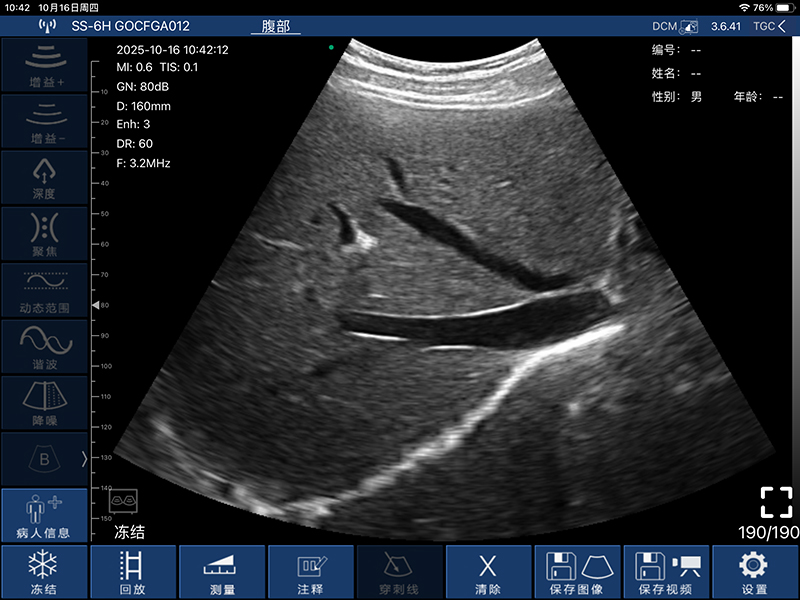

• 扫描方式:电子阵列扫描

• 探头频率:3.2/5.0MHz

• 增益30db-105db

• 扫描深度:90/160/220/305mm,可调

• 显示模式:B、B/M、Color、PW、PDI

• 图像调节:增益、焦点、反相脉冲谐波、降噪